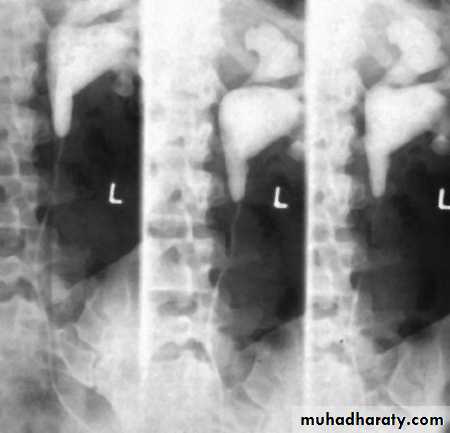

Retrocaval ureter :

The middle third of right ureter curve medially behind the IVC , then laterally to regain it’s normal position , this lead to obstruction of upper third of ureter.